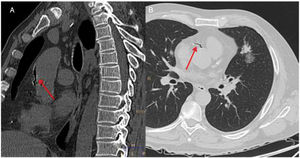

Tras realizar la BAG se efectuó una TC torácica de control. En dicha exploración se observó un pequeño neumotórax izquierdo y una hemorragia local perinodular, visualizándose además, una pequeña cantidad de aire en la aorta torácica ascendente y en la arteria coronaria derecha (fig. 1). A continuación, el paciente sufrió un cuadro brusco de disminución del nivel de conciencia (escala de coma de Glasgow 5/15), con hipotensión arterial (TA 80/40mmHg), bradicardia (FC 35lpm) y marcada desaturación (saturación de oxígeno por pulsioximetría menor al 50%), precisando intubación orotraqueal y conexión a ventilación mecánica. Posteriormente se le realizó un electrocardiograma que mostró alteraciones compatibles con un bloqueo auriculoventricular completo y un síndrome coronario agudo, con elevación del segmento ST en la cara anterior. Ante estos hallazgos, se pautó atropina y una perfusión de noradrenalina, con recuperación posterior de la frecuencia cardiaca y la TA. Ante la posibilidad de que el paciente sufriera además una embolia gaseosa cerebral, dado el cuadro neurológico descrito, se efectuó también una TC craneal, que no mostró alteraciones intracraneales de carácter agudo, siendo el paciente ingresado en la unidad de cuidados intensivos (UCI) para monitorización y seguimiento.